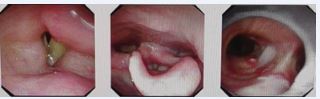

Intervention: Under general anesthesia, a V-V ECMO assisted thyroid biopsy and tracheostomy were performed. Intraoperative resection of anterior thyroid tissue for pathological diagnosis, with subsequent tracheal exposure and tracheostomy. Pathological examination confirmed diffuse large B-cell lymphoma (germinal center origin, Ann Arbor stage IV XB). Postoperatively, the patient was transferred to hematology for further treatment. Follow-up CT at two months showed significant tumor regression and a stable tracheostomy (Figure 2). Electronic laryngoscopy showed no obvious tracheal stenosis (Figure 3).Follow-up is ongoing

Figure 3 Laryngoscopy reveals left vocal cord paralysis with normal right vocal cord mobility and no significant tracheal stenosis.

Examination: Physical examination revealed inspiratory dyspnea with mild sternal retractions. Laryngoscopy revealed a 4 mm scar-induced tracheal stricture. Normal vocal cord mobility (Figure 4). Neck CT confirmed a 1.5 cm tracheal stenosis with a 4 mm narrowest diameter (Figure 5).

Figure 4 Laryngoscopy demonstrates symmetric vocal cord mobility without glottic stenosis. A circumferential scar-induced stenosis (approximately 4mm in diameter) is observed in the subglottic cervical trachea.